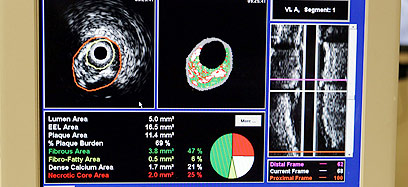

"המערכת הזאת, שנקראת Inter Vascular Ultrasound) IVUS), מאפשרת קבלת תמונה ברמה של דיוק מיקרוסקופי של עורקי הלב", אומר ד"ר שמואל פוקס, מנהל שירות הצנתורים בבית החולים השרון. "יתרון נוסף שלה הוא שהמידע שמתקבל באמצעותה משודר בזמן אמת לצג טלוויזיה – דבר שמאפשר לרופא לקבוע את מידת הטרשת בעורקי הלב ואת הרכבה, כלומר לבדוק אם הטרשת היא רכה ופריכה או קשיחה ומסוידת. המידע הזה רב ערך, ויש לו השלכות טיפוליות מהותיות, כמו החלטה אם לשלוח את החולה לצנתור טיפולי או לטפל בו באמצעות תרופות".

"למעלה מ-20 אלף חולים בישראל נזקקים מדי שנה לצנתור טיפולי לשם פתיחת עורק חסום, ועוד כ-30 אלף חולים עוברים מדי שנה צנתור אבחוני", אומר פרופ' רן קורנובסקי, מנהל מכון הצנתורים בבית החולים בילינסון. "הבדיקה החדשה מספקת מידע מדויק ומפורט לגבי פעילות הלב ומצב העורקים שמזינים אותו, כמו קוטר חלל העורק, קוטר כלי הדם, עוצמת ההיצרות ונקודת ההיצרות הקריטית".

כיצד מתבצעת הבדיקה? "מערכת האולטרסאונד התוך עורקית החדשה מאפשרת לראשונה לאפיין את אופי השכבה הטרשתית ולשרטט את גבולותיה במדויק", מסביר פרופ' מילר. "במהלך הצנתור האבחוני מוחדר באמצעות קטטר, דרך עורק היד או המפשעה, מתמר אולטרסאונד שמבוסס על פענוח גלי קול.

"בעזרת המערכת הממוחשבת מיתרגמים אותות גלי הקול לתמונה תלת מימדית צבעונית. כל צבע מסמל חומר רקמתי אחר, ויחד יוצרים הצבעים את הרכב הרקמה כולה. לדוגמה, צבע לבן מסמל ריכוז סידן, צבע אדום מסמל ריכוז שכבת שומנים וכדומה.